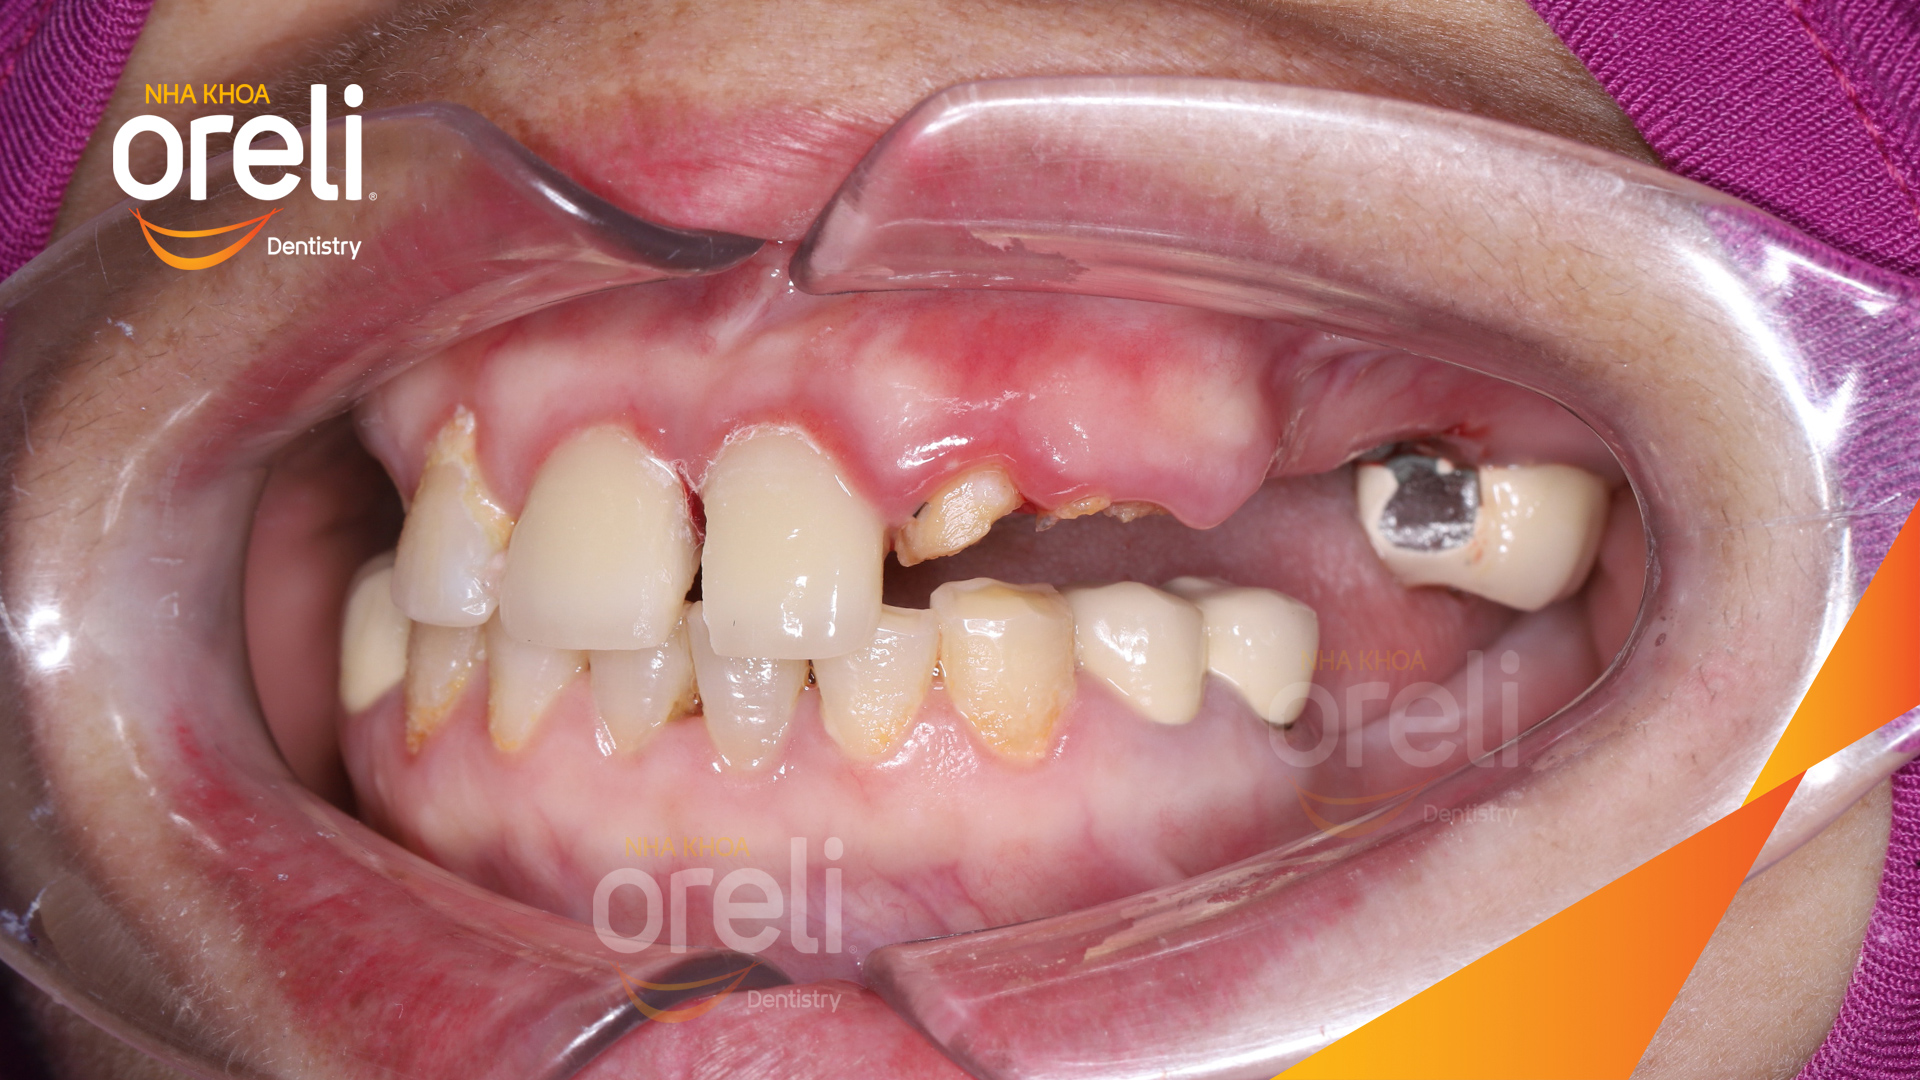

Tình trạng: Cầu răng sứ hàm trên lâu ngày gãy, viêm nướu, chân răng lung lay

Giải pháp: Cắt cầu răng sứ, nhổ răng, trồng răng implant

Hình ảnh thực tế